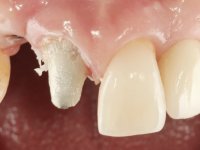

Segunda Fase.

Após 5 anos da primeira intervenção, a paciente surge na consulta com uma peri-implantite nos implantes colocados no local dos dentes 1.2 e 4.6. Começamos por abordar a peri-implantite no local do dente 2.2. Foi feita uma ponte provisória de laboratório em acrílico com 2 elementos. O dente 1.1 como pilar e o 1.2 como pôntico, este último apresentava um apoio distal. A coroa do 1.2 foi removida do coto com um corte longitudinal feito com turbina e depois foi fraturada com um mini luxador. O coto foi de seguida desaparafusado do implante. Fez-se o mesmo procedimento para remover a coroa do 1.1. O dente 1.1 foi re-preparado e a ponte provisória foi rebaseada em boca com acrílico autopolimerizável. Feito o correto acabamento e polimento da provisória foi feita a sua cimentação temporária com cimento de policarboxylato. Numa consulta posterior. foi feita a remoção da ponte provisória, feita a cirurgia para explantação do implante, colocou-se um novo implante e fez-se a regeneração óssea da zona com uma membrana não reabsorvível. 3 meses após foi removida a coroa do implante colocado no 4.6. Foi feito um corte horizontal com turbina na zona cervical e com um mini luxador descolou-se a coroa do coto. Após este procedimento fez-se a explantação do implante. Após 6 meses foi colocado um novo implante no local do 4.6. Após a osteointegração foi feita a impressão com a técnica de moldeira aberta e foi confecionada em laboratório uma coroa aparafusada sobre o implante. Aprovada pela paciente foi apertada definitivamente em boca. Após 1 mês removemos a ponte provisória antero-superior, reforçamos o dente 1.1 com um poste intra- radicular e reconstruimos o coto com uma resina de polimerização dual. Nessa mesma consulta expomos o implante colocado no 1.2 e fizemos uma impressão pela técnica de moldeira aberta com silicone de dupla viscosidade e presa rápida. No laboratório foi feita uma ponte provisória de 2 elementos, aparafusada sobre o implante e cimentada sobre o dente. A primeira ponte provisória foi removida e colocada a segunda aparafusada sobre o implante. A linha de acabamento cervical do 1.1 foi rebaseada com resina composta durante o aperto do parafuso do implante. Depois foi removida, foram feitos os acabamentos e finalmente apertada sobre o implante e cimentada temporariamente sobre o dente. Após 2 meses de maturação dos tecidos moles em função do perfil de emergência criado pela nova ponte provisória, pudemos avaliar a estética conseguida em conjunto com a paciente. Neste longo processo o dente 2.1 teve que fazer um tratamento endodôntico. Decidiu-se assim fazer também uma coroa no dente 2.1.O dente 2.1 foi preparado na mesma consulta em que se fez a impressão ao implante. A ponte provisória foi utilizada para individualizar a peça de transferência, copiando o seu perfil de emergência e em seguida foi realizado o afastamento gengival com caolino. A impressão foi feita com a técnica de moldeira aberta com silicone de dupla viscosidade e presa rápida. Após a escolha da cor, a impressão foi enviada  para o laboratório onde foram confecionadas 2 coroas  com infraestrutura em Zr. revestidas a cerâmica para os dentes 1.1 e 2.1 e uma coroa aparafusada sobre o implante no dente 1.2. O trabalho final foi aprovado pela paciente e foi colocado definitivamente em boca. A coroa sobre o implante foi aparafusada com 35 N e as coroas foram cimentadas com cimento de ionómero de vidro reforçado com resina.